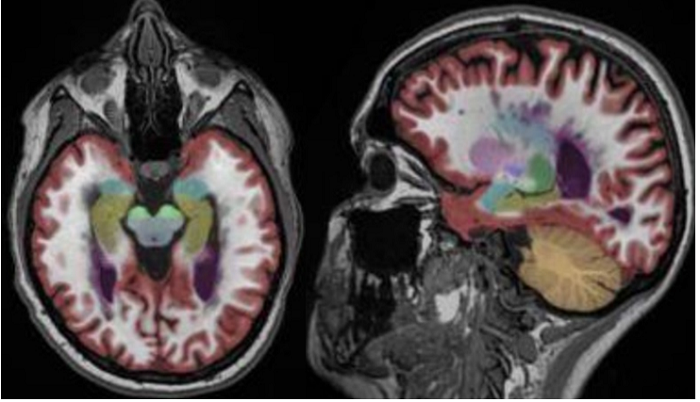

医生诊断用的MRI图像

在现在的医疗机构,医生获取患者的MRI图像后,往往是根据经验判断患者的大脑是否萎缩。因为用经验判断的东西差异化很大,所以漏诊的现象时常出现。

脑医生的云平台工作流程是这样的,医生将受试者数据上传,脑医生通过图像处理、大数据运算和统计学分析等方法将医生的经验量化、标准化,最后得到精确的诊断报告

MRI图像的最优选择

在现实的临床中,CT、MRI、PET/SPECT各种影像都可以用来诊断老年痴呆症。通过比较,脑医生首先选择了MRI图像作为突破口。

王思伦表示:“MRI图像有很多优势:第一,在获取MRI图像时对人体没有放射性损伤。第二,MRI的结构性扫描在临床应用广泛,非常容易获得。第三获取成本低,时间短,通常情况下,患者拍MRI图像的成本在几百元左右,相比于PET\CT要便宜的多,另外拍摄时间短,不会对临床工作带来很多干扰。” 因此美国放射科学会也推荐结构MRI图像是诊断AD(阿尔兹海默症)的最佳影像学方式